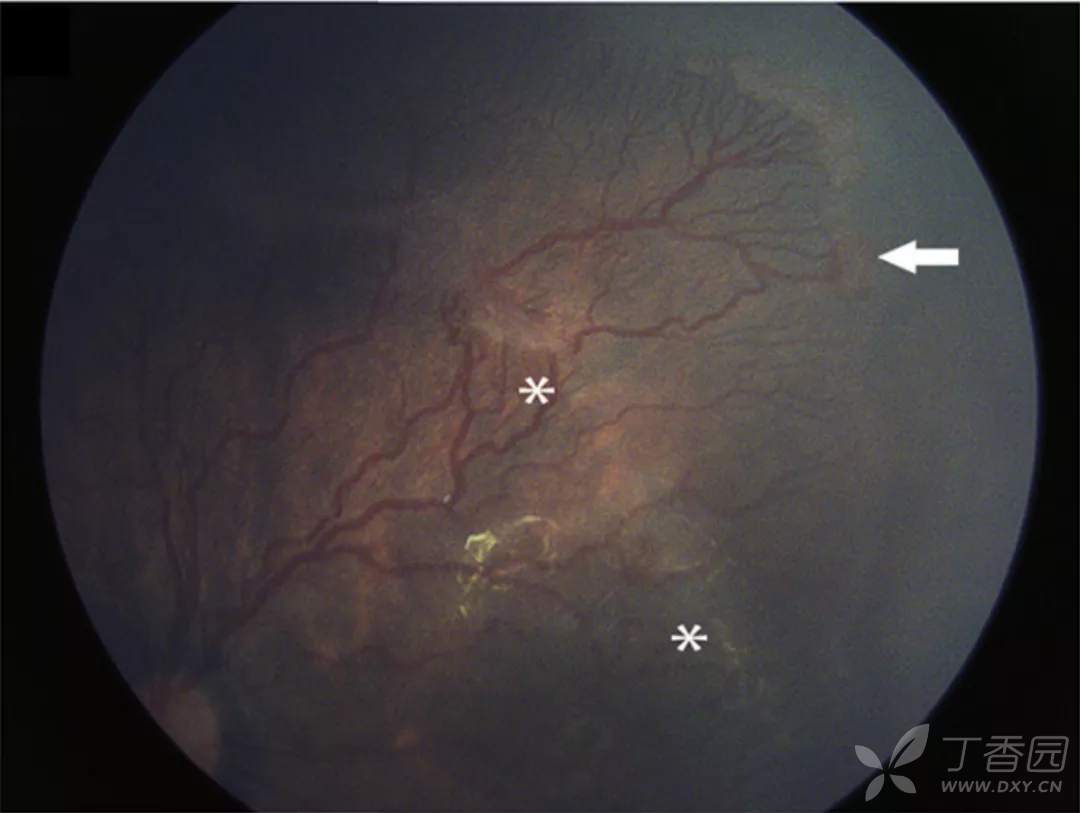

06、急性早产儿视网膜病变4期:部分视网膜脱离

图. 4B期视网膜脱离伴视网膜下出血和黄斑脂质渗出。